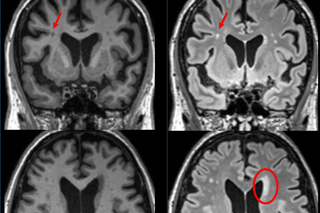

The Alzheimer’s Disease Neuroimaging Initiative (ADNI) unites researchers with study data as they work to define the progression of Alzheimer’s disease. Researchers collect, validate and utilize data, including MRI and PET images, genetics, cognitive tests, CSF and blood biomarkers as predictors of the disease. Since its launch in 2004, the study has made major contributions to Alzheimer's disease research, enabling the sharing of data between researchers around the world.

The Indiana Memory and Aging Study uses brain imaging and genetic biomarkers, cognitive and sensory testing and behavior ratings to study memory processing as it relates to aging in the brain.

Since 2016, the Social Networks and Alzheimer’s Disease leverages neuroimaging biomarkers to examine social and biological mechanisms underlying relationships between personal social networks and patterns of neurodegeneration in early stages of Alzheimer's disease.